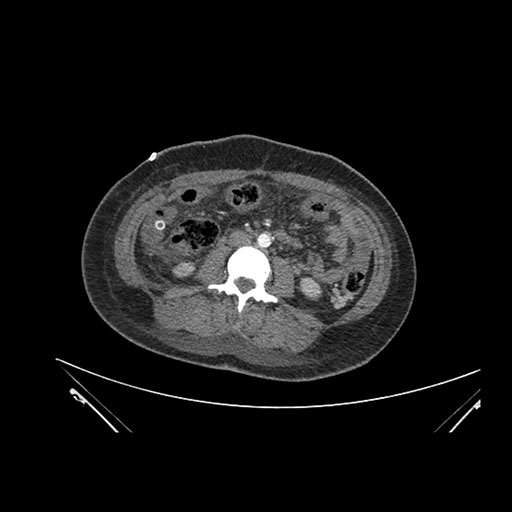

Axial Arterial

Axial Venous

Imaging analysis

Based on initial findings, which issue(s) would you be most concerned about?